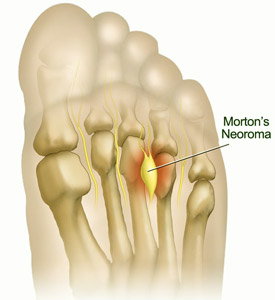

More accurately Morton's neuroma (also known as Morton's metatarsalgia, Morton's neuralgia, plantar neuroma and intermetatarsal neuroma) and can be considered seperately from the more general (and potentially more worrying) term 'neuroma'.

Despite it's name the condition was first correctly described by a chiropodist named Lewis Durlacher in 1845.

This is a benign growth of fibrous tissue formation around an area of the intermetatarsal plantar nerve, most commonly of the third and fourth intermetatarsal spaces and is often characterised by pain and/or numbness, sometimes relieved by removing footwear.

At Chuckle Shoes we use orthotics and special construction techniques to create the correct footwear around the individual case.